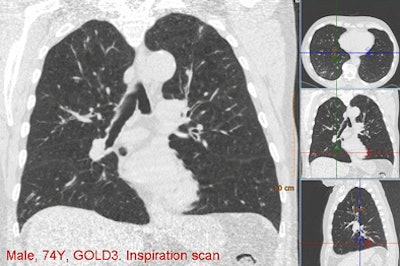

| Above, images from the inspiration scan of a 74-year-old man diagnosed as GOLD stage 3. There is emphysema (dark areas) throughout the lungs, and only the lower right lobe is not substantially affected. Below is the overlay image based on thresholding at -950 HU, including the percentages for each lobe as a whole. Four lobes, except the lower right, are above their cutoff values, meaning that this patient has an emphysema-dominant COPD phenotype. The right lower lobe was also not affected by air trapping. All images courtesy of Bram van Ginneken, MD, PhD. |